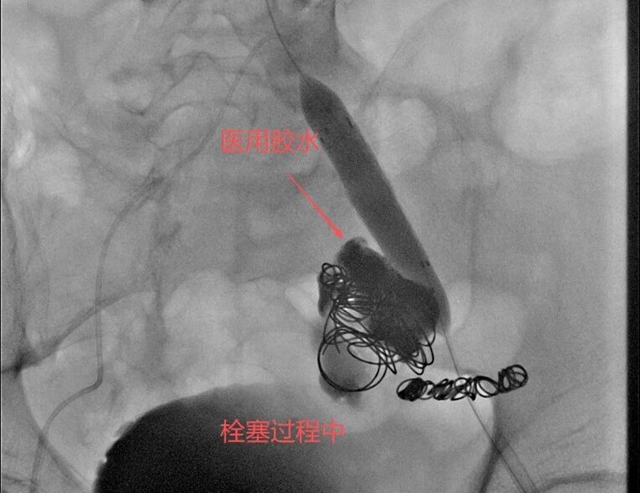

徐燕能博士选择了弹簧圈+医用胶水的复合栓塞技术——这项技术在介入医学界被戏称为“钢筋水泥”结构。“弹簧圈就像钢筋,能够在动脉瘤内形成一个稳定的框架结构;医用胶水则是水泥,填充在弹簧圈形成的框架中,迅速固化形成致密的栓塞体。”

随着弹簧圈被精准放置到动脉瘤腔内,医用胶水随后注入,两者结合形成了坚固的“钢筋水泥”结构,牢牢封堵了破裂处。

完成动脉瘤栓塞后,徐燕能博士团队并未停止。他们清楚知道,单纯栓塞动脉瘤可能还不够。

下一步是在左侧髂总-髂外动脉植入覆膜支架,这一步至关重要。覆膜支架的作用是隔绝动脉瘤,重建正常血流通道,防止血流再次冲击已经脆弱的血管壁。